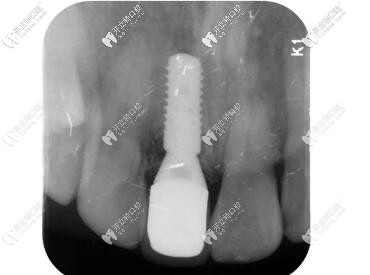

術(shù)后CBCT顯示植入正確的三維位置,種植體唇側(cè)骨量充足;

瑞士iti鈦親水BL 4.1mm*10mm種植體